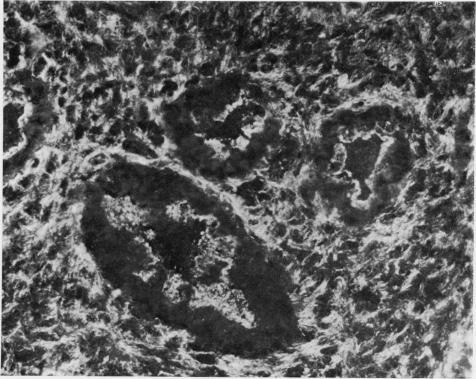

Cryostat sections and established in vitro cultures of dimethylnitrosamine(DMN)-induced renal mesenchymal tumours and monolayer cultures of transformed kidney cells derived from rats treated with a carcinogenic dose of DMN were examined by indirect immunofluorescence with human serum containing smooth muscle antibody. Eight mesenchymal tumours examined showed filamentous cytoplasmic staining of spindle cells infiltrating between renal tubules, whilst in normal kidneys interstitial cells were only weakly positive. In established in vitro cultures from 6 mesenchymal tumours, different patterns of staining were observed in morphologically different cell forms, ranging from fine filamentous staining in giant cells to diffuse cytoplasmic fluorescence in small bipolar cells, and cell outline staining in polygonal cells. In addition filamentous staining of microvillous projections and nucleolar staining were observed in some tumour cells. Monolayer cultures of transformed kidney cells showed strong staining of coarse, randomly-orientated cytoplasmic filaments, whilst fibroblasts cultured from normal rat kidney demonstrated an ordered array of fine, parallel filaments. Specificity of the immunofluorescent staining reaction was established by failure to obtain staining with normal serum, with smooth muscle antibody serum neutralized by homogenates of smooth muscle or extracts containing actin derived from smooth muscle. These results indicate that there is an apparent increase of actin-like contractile microfilaments in transformed cells and in renal mesenchymal tumours. The cytoplasmic contracile microfilaments in these cells may play a role in tumour cell mobility and invasion.

采用含平滑肌抗体的人血清通过间接免疫荧光法检测了二甲基亚硝胺(DMN)诱导的大鼠肾间充质肿瘤的低温切片和体外培养物,以及用致癌剂量的DMN处理的大鼠来源的转化肾细胞的单层培养物。所检测的8个间充质肿瘤显示,浸润于肾小管之间的梭形细胞的胞质呈丝状染色,而在正常肾脏中,间质细胞仅呈弱阳性。在来自6个间充质肿瘤的体外培养物中,在形态不同的细胞形态中观察到了不同的染色模式,从巨细胞中的细丝状染色到小双极细胞中的弥漫性胞质荧光,以及多角形细胞中的细胞轮廓染色。此外,在一些肿瘤细胞中还观察到微绒毛突起的丝状染色和核仁染色。转化肾细胞的单层培养物显示出粗大、随机排列的胞质细丝的强染色,而从正常大鼠肾脏培养的成纤维细胞则显示出排列有序的细平行细丝。通过用正常血清、被平滑肌匀浆或含平滑肌肌动蛋白提取物中和的平滑肌抗体血清未能获得染色,确定了免疫荧光染色反应的特异性。这些结果表明,在转化细胞和肾间充质肿瘤中,肌动蛋白样收缩微丝明显增加。这些细胞中的胞质收缩微丝可能在肿瘤细胞的迁移和侵袭中起作用。